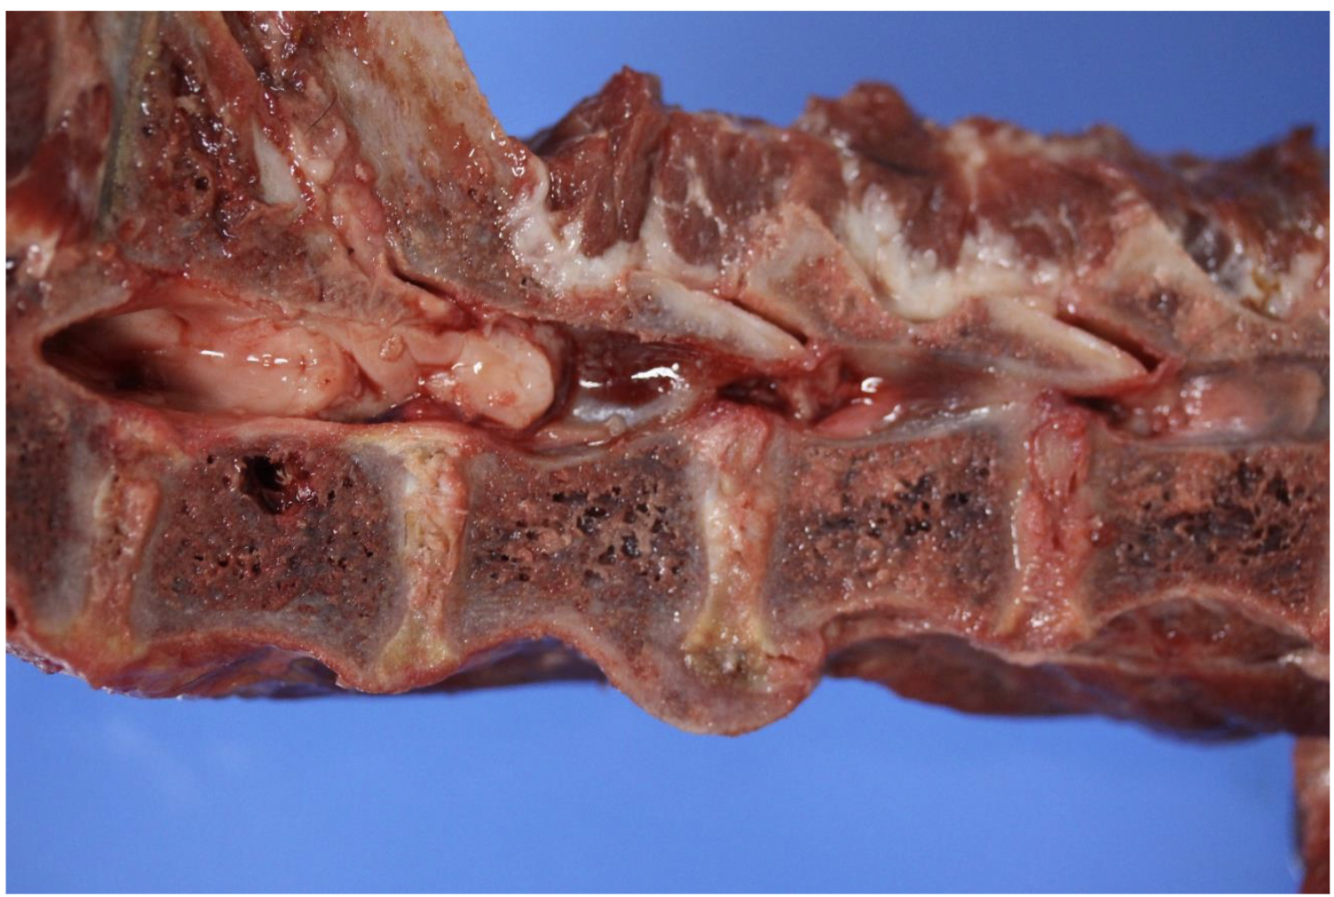

Spondylosis

Between T13 and L1

Osteophyte proliferation producing the protrusion

increased mobility of the vertebra –> osteophyte proliferation –> IDD

Spondylosis deformans

Suppurative Osteomyelitis

Inspicated (dried suppurative exudate). Destruction of vertebrae (circle around yellow).

Lesion may be involving spinal chord, so potentially could add Vertebral Osteomyelitis

Etiologic Cause: Bacterial

Myelopathy = degenerative changes of the spinal chord –> myelitis